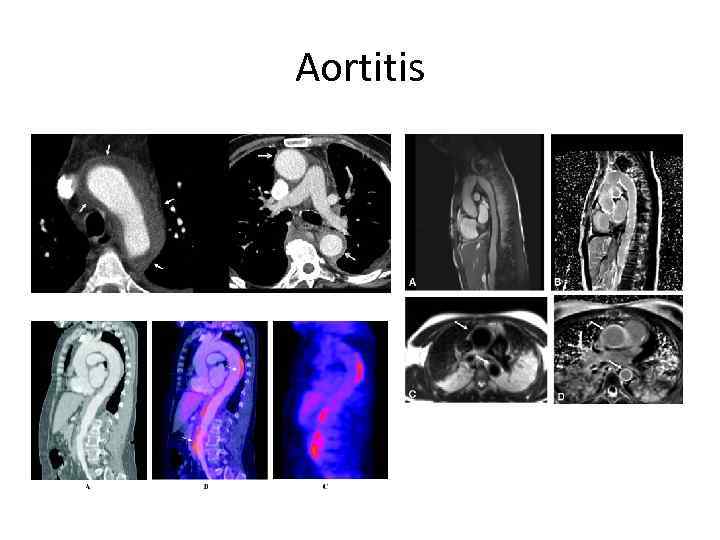

Aortitis